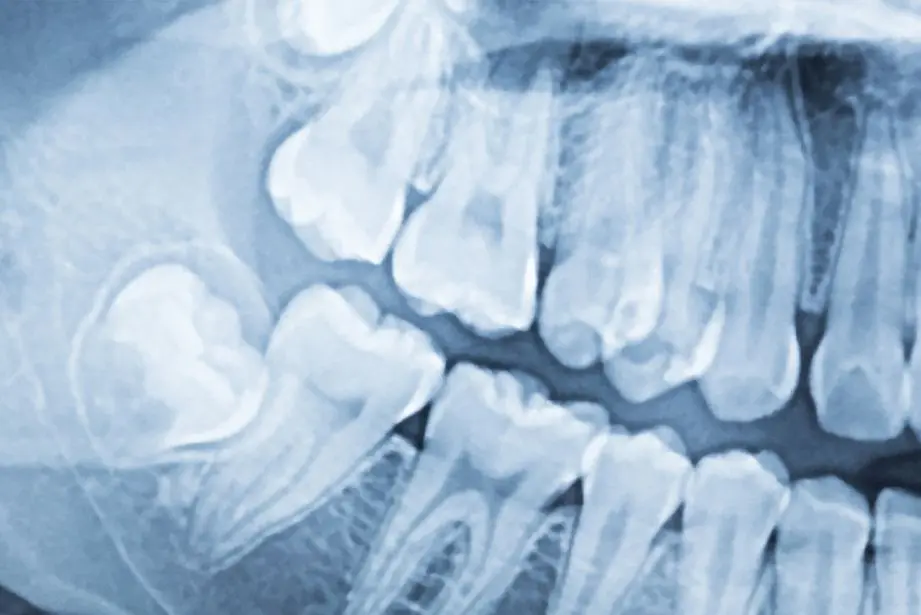

Zašto vam je potrebna rendgenska i/ili CT snimka?

Nekad nam sami pregled usne šupljine ne govori sve što trebamo znati. Često ono što je oku vidljivo zna zavarati, a pravi problem se može kriti i ispod zubnog mesa, duboko u zubnim stukturama, ili u samoj zubnoj čeljusti. 2D i 3D rendgenska dijagnostika ne ostavljaju prostora krivim procjenama i daju pravu sliku dentalnog stanja pacijenta.

Ortopan ili rendgenska snimka zubi je panoramska slika zubi koja pokazuje trenutačno stanje usne šupljine i koja se radi prije bilo kojeg stomatološkog zahvata. Ortopan i CT snimka posebno su bitni kod planiranja implantoloških zahvata i općenito kirurgije.

Uz ortopan, CT, točnije računalno navođena tehnologija u današnje se vrijeme postavila kao neophodna metoda dijagnostike. Ona svojim mogućnostima rekonstrukcije slike podiže kvalitetu i preciznost rada. CBCT snimka našim stručnjacima omogućava provjeru gustoće kostiju što je glavni preduvjet za ugradnju implantata.